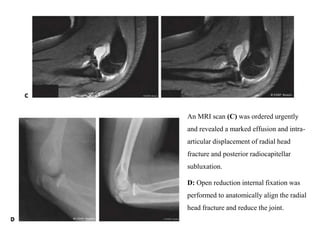

An MRI scan (C) was ordered urgently

and revealed a marked effusion and intra-

articular displacement of radial head

fracture and posterior radiocapitellar

subluxation.

D: Open reduction internal fixation was

performed to anatomically align the radial

head fracture and reduce the joint.